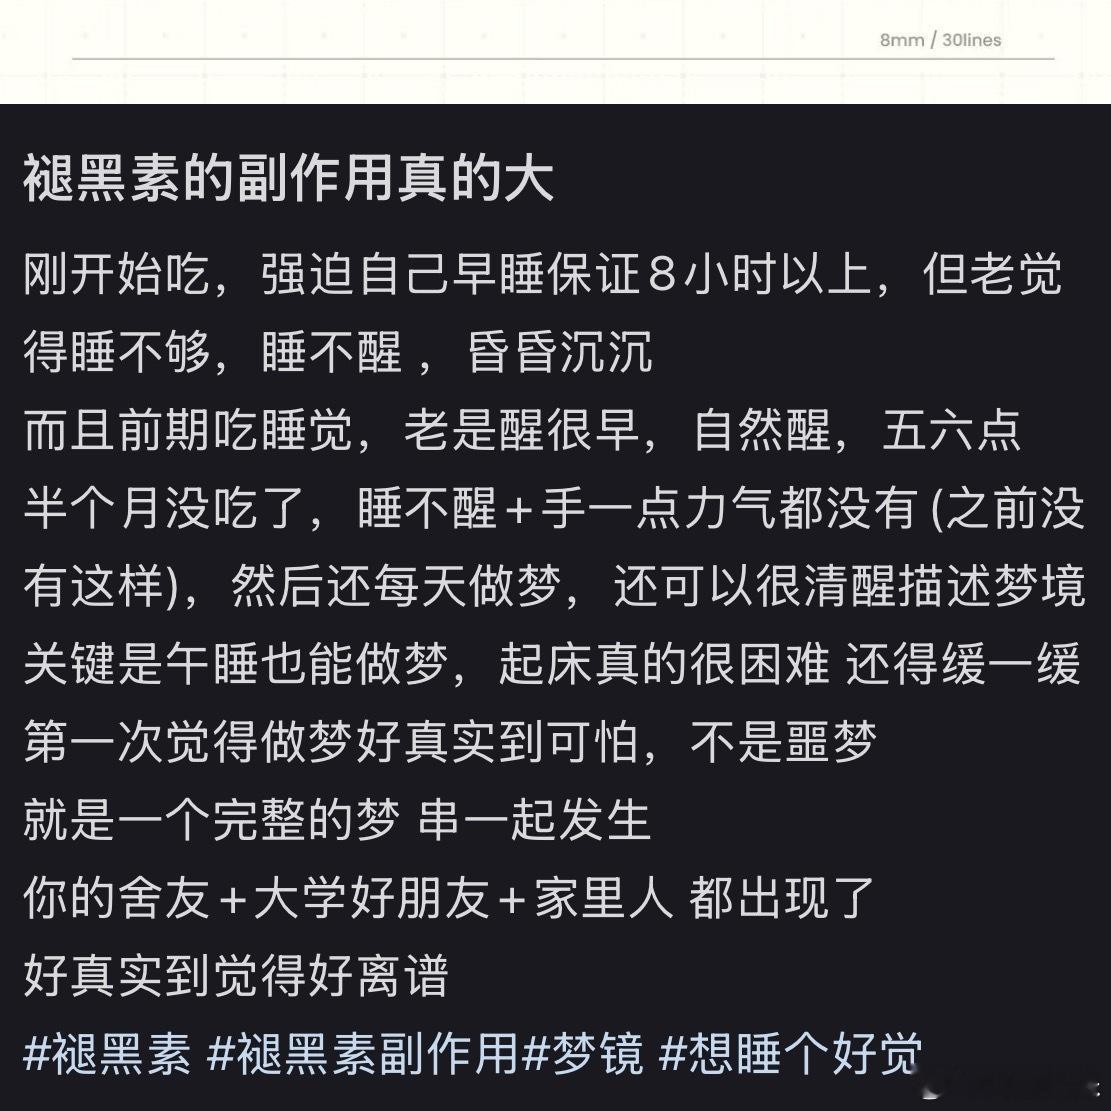

大家还真是要少吃褪黑素,我感觉就是在恶性循环的过程,搜了一下原来大家都这样。

晚上12点入睡整晚都在做噩梦(什么乱七八糟都有),加起来睡眠确实能到8小时,但白天依旧很累。不吃褪黑素每天晚上睡眠虽然老醒,至少会有3、4小时深度睡眠(不做噩梦)。

最佳最优的办法就是,建议睡前一两小时体力劳动,与脑力劳累正比一下,这样入睡就会轻松多一点[跪了]